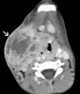

Thoracic extension of neck abscess

Mediastinitis is inflammation of the tissues in the mid-chest, or mediastinum. It can be either acute or chronic. [Source: Wikipedia ]